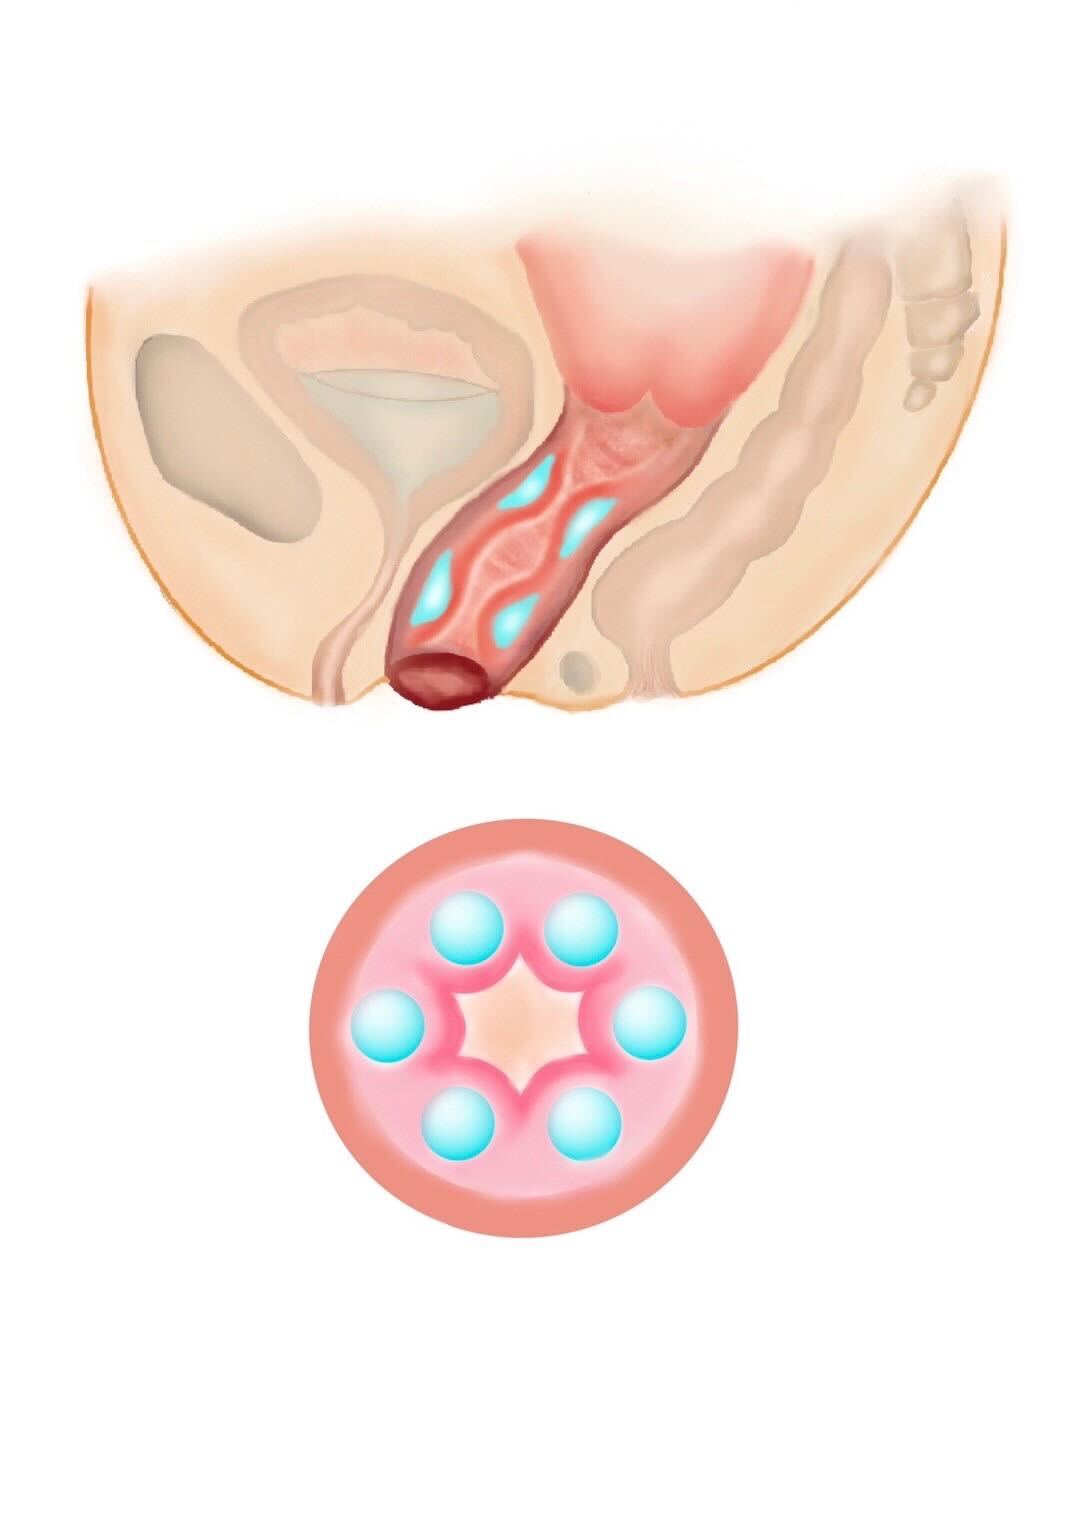

他にもヒアルロン酸注入や再生治療、レーザーなどの治療もありますが、腟壁縮小手術、腟括約筋縫縮術はあらゆる治療の中で最も効果の高い治療になります。腟壁縮小手術では、産後に緩んでしまった腟壁を腟の奥から切開し縮小します。腟周辺の筋肉を縮小縫合し、新たに腟のヒダを形成することが可能です。

また同時に入り口付近にある腟括約筋を縫縮すると、入り口から腟の奥まで縮小され、高い効果が得られます。 腟は直腸に接するようにすぐ前に位置しますので、繊細な作業を要し、高い技術が必要です。

名器形成(10ccまで)

膣内に上下にヒアルロン酸を注入し、パートナー共に性行為時の感度を高めることが可能です。